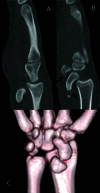

Palmar Divergent Dislocation of the Scaphoid and Lunate

Teaching Point: Palmar dislocation of the scaphoid and lunate is an extremely uncommon injury that warrants early diagnosis and treatment to avoid complications such as median nerve dysfunction, avascular necrosis, and premature osteoarthritis.